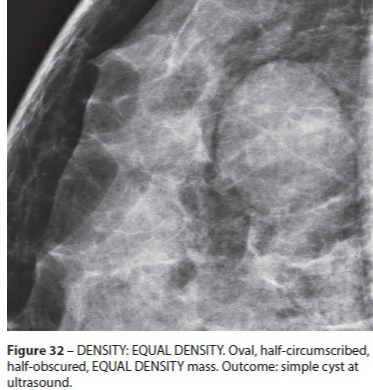

Isodense

- Comme le tissus fibroglandulaire

- 20% de chance de tumeur